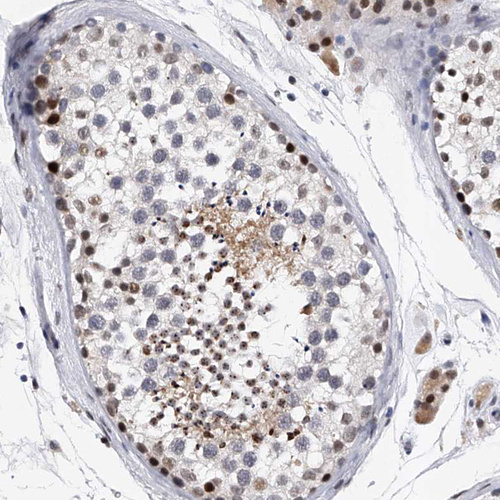

Immunohistochemical staining of human skin shows moderate to strong nuclear positivity in squamous epithelial cells.